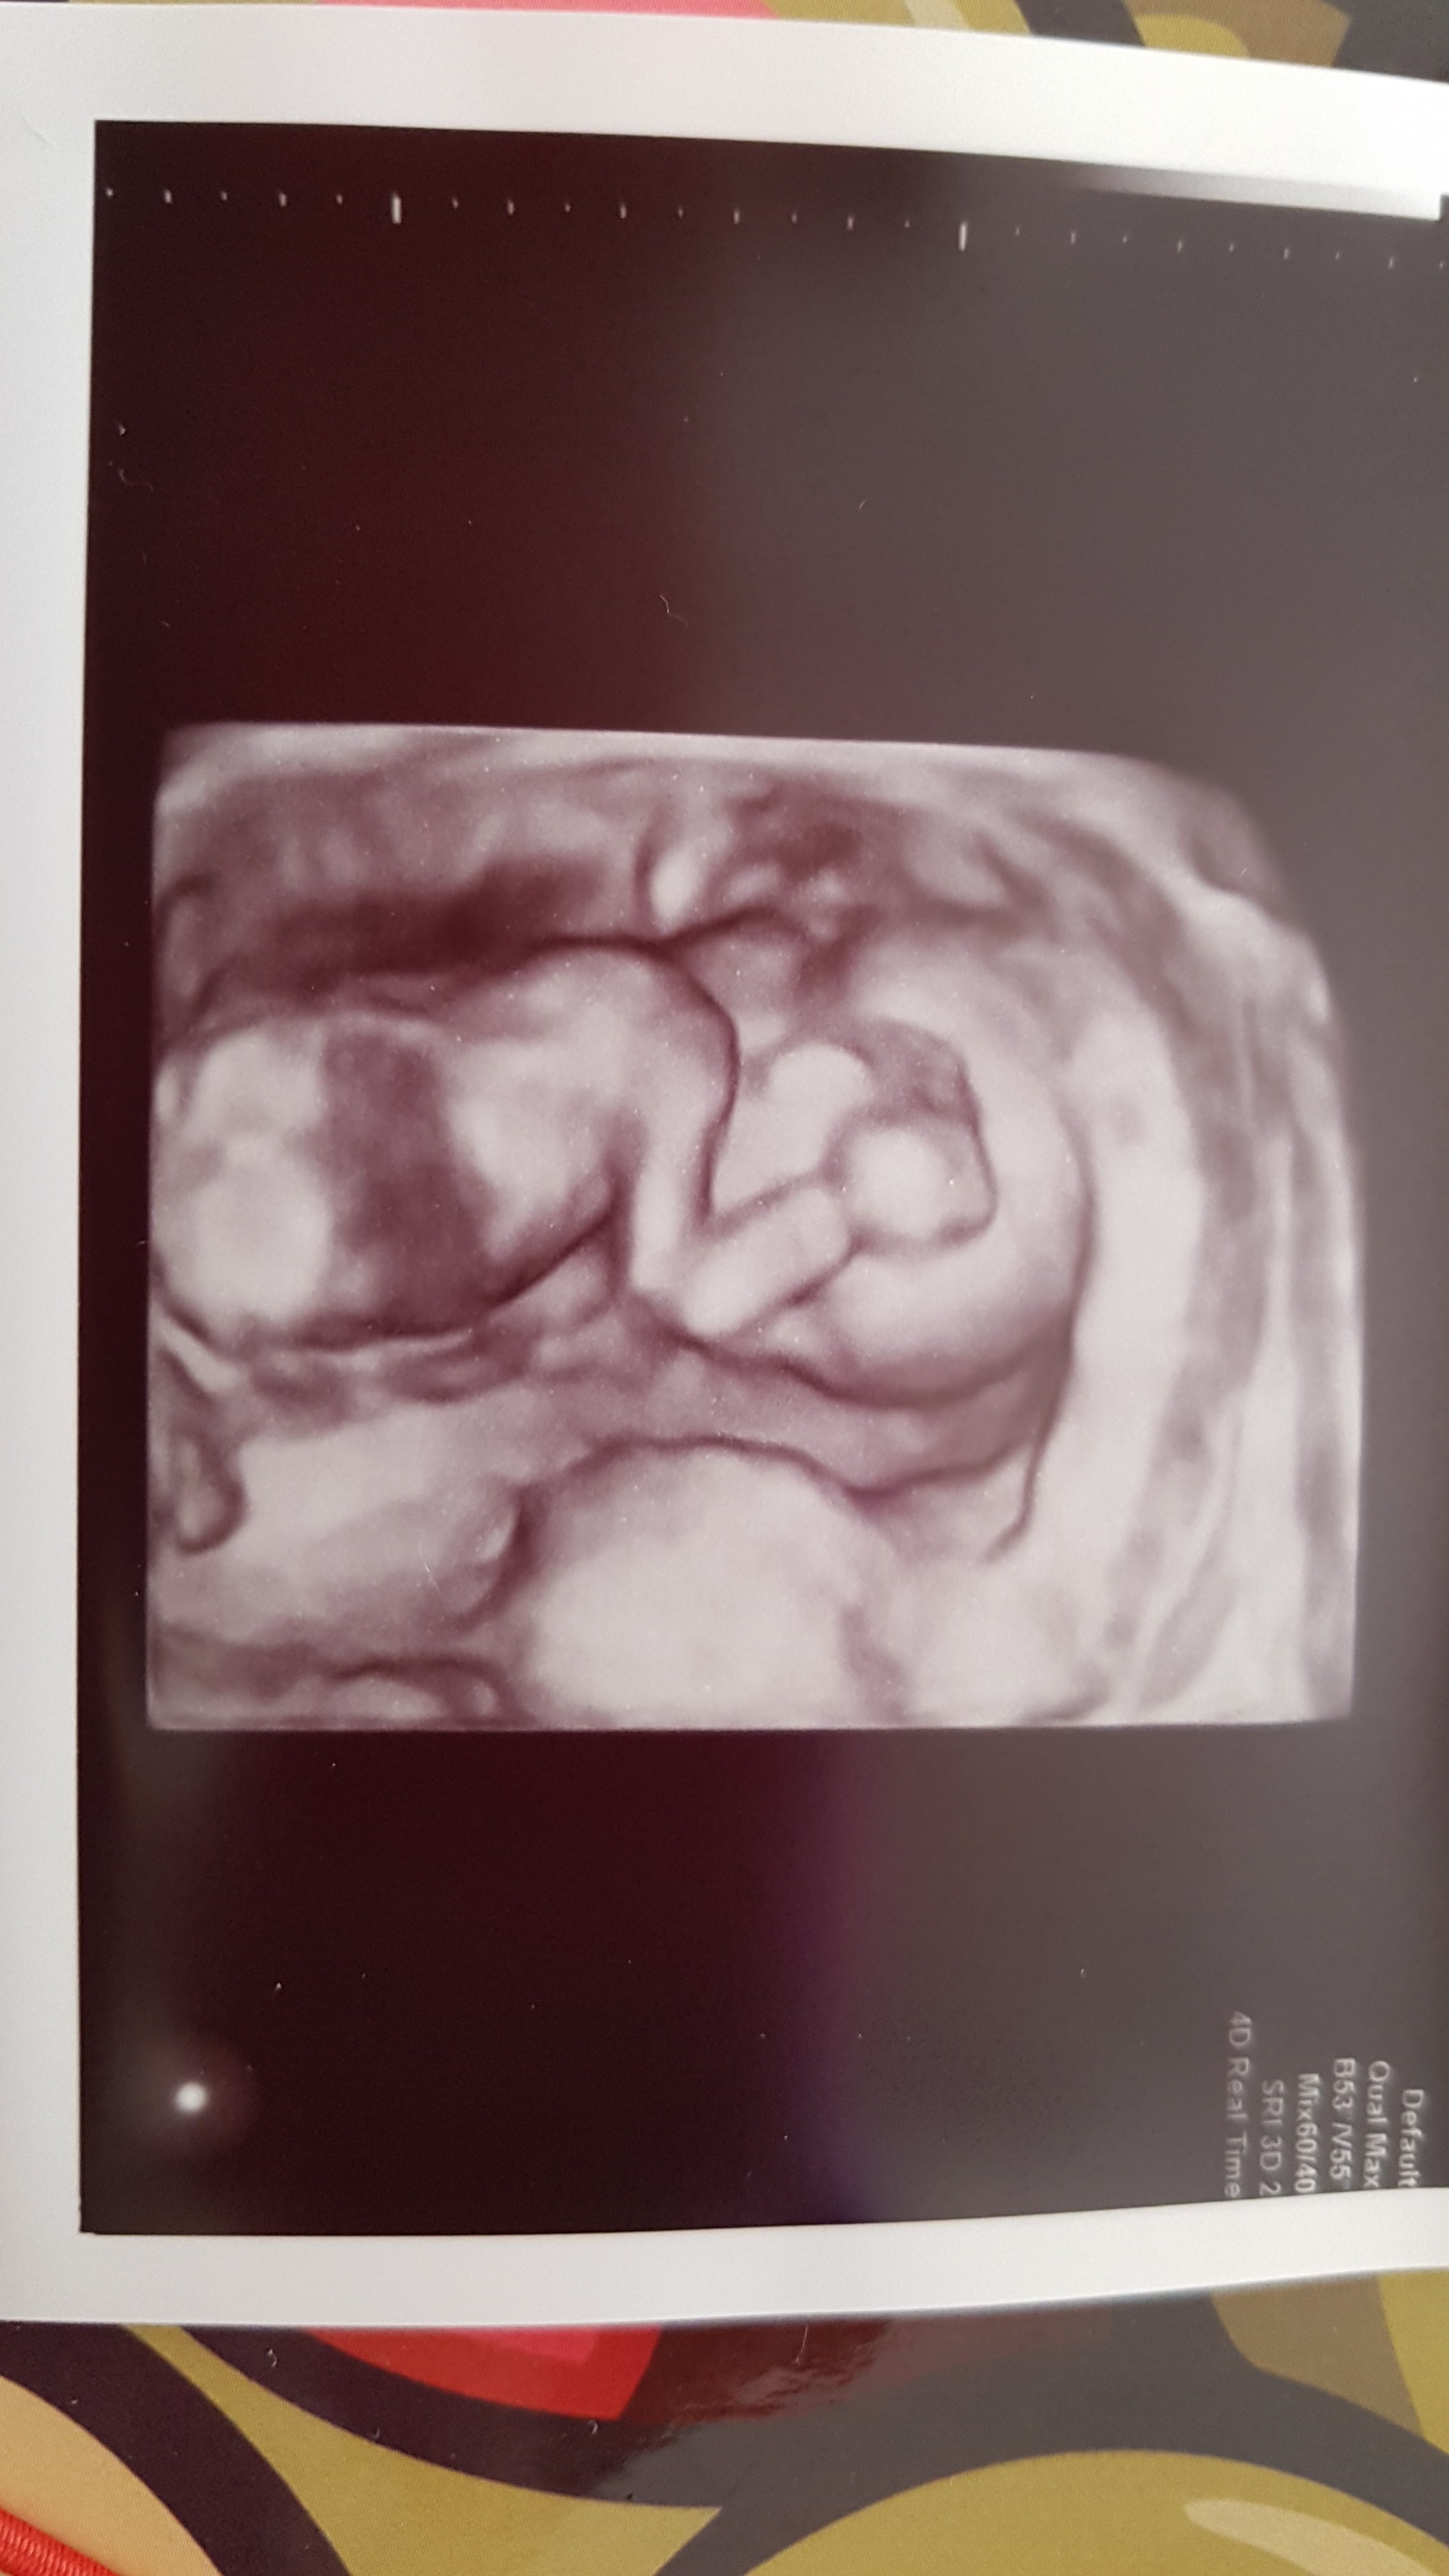

Marcelinie nie urósł siusiak dalej jest baba i ma się świetnie

20170726_163407.jpg

• 20170726_163407.jpg

647,2 KB · Wyświetleń: 2 974